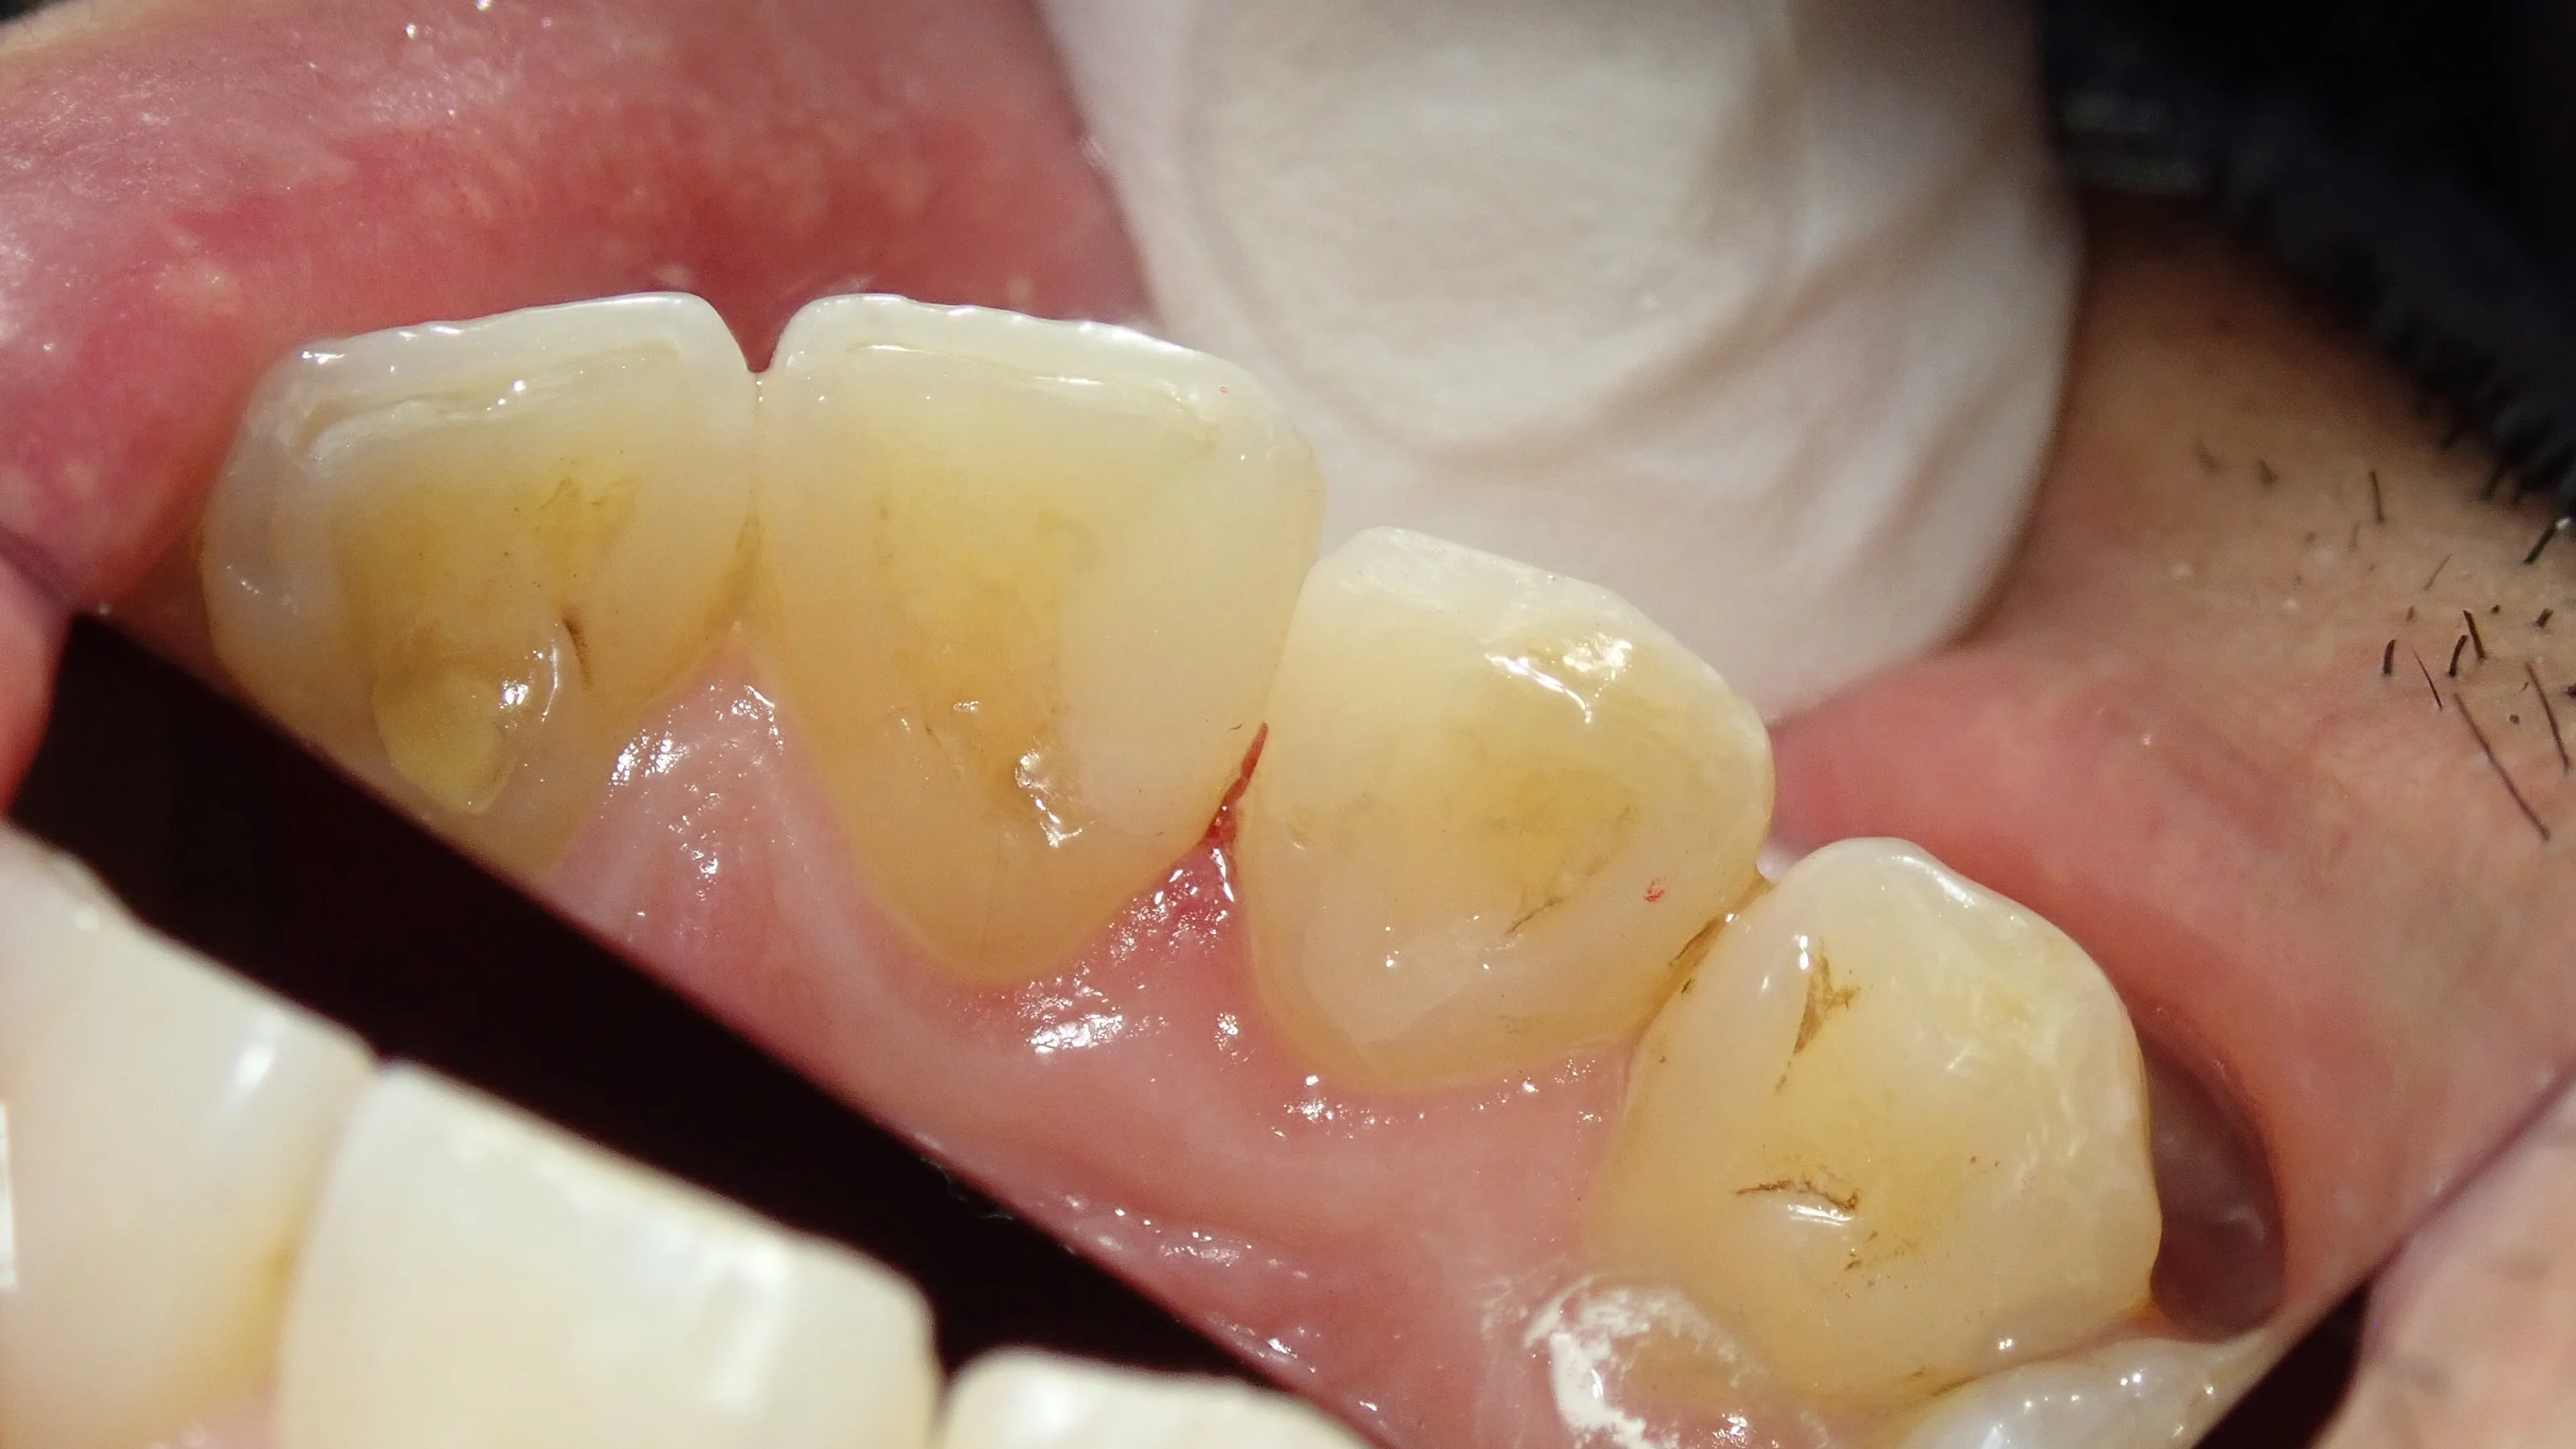

手前側の古い詰め物を除去したのがこちらです。

表から見た写真と

裏から見た写真です

裏から見ると内面がくろーくなってるのが分かりやすいですね。